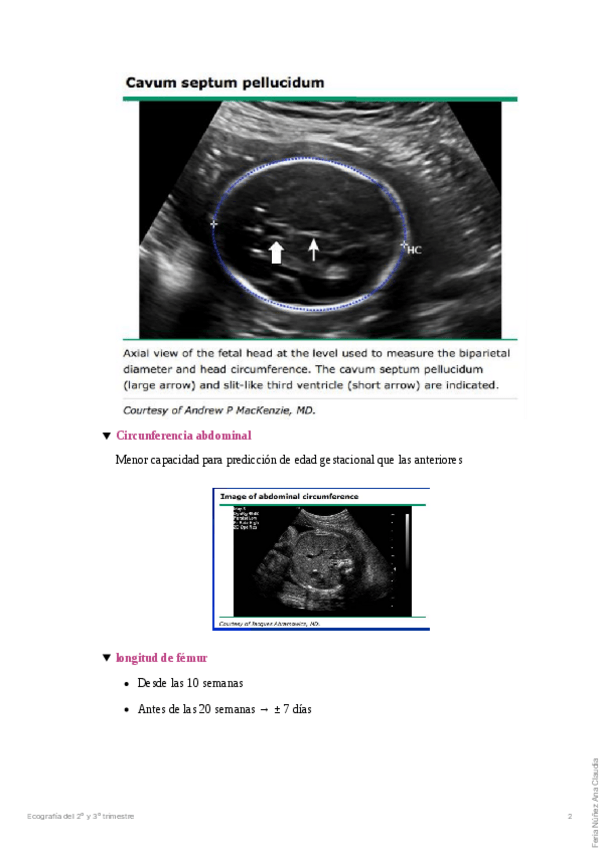

He publicado nuevos apuntes de 10º Habilidades en Ginecología y Obstetricia: Ecografia del II y III trimestre.pdf